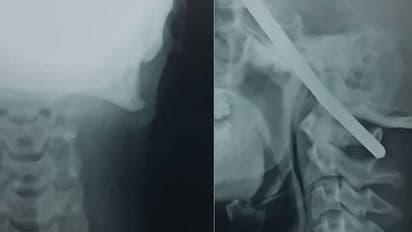

നിര്മ്മാണത്തൊഴിലാളിയായ സഞ്ജയ് ഒരു കിണര് വൃത്തിയാക്കുന്നതിനിടെയായിരുന്നു അപകടം. കയറില് തൂങ്ങി, കിണറ്റില് നിന്ന് മുകളിലേക്ക് കയറുന്നതിനിടെ അബദ്ധത്തില് താഴേക്ക് വീഴുകയായിരുന്നു. മുപ്പത്തിയഞ്ച് അടി താഴ്ചയിലേക്ക് വീണ സഞ്ജയുടെ വലത് നെറ്റിയിലൂടെ നീണ്ട കമ്പി കുത്തിക്കയറി. തുളഞ്ഞുകയറിയ കമ്പി ഇടത്തേ നെറ്റിയുടെ വശത്ത് കൂടി പുറത്തേക്കെത്തി.

കൂടെയുണ്ടായിരുന്നവര് അടുത്തുള്ള ആശുപത്രിയില് കൊണ്ടുപോയെങ്കിലും അവിടെനിന്ന് നാഗ്പൂരിലുള്ള വലിയ ആശുപത്രിയിലേക്ക് മാറ്റാന് ഡോക്ടര്മാര് നിര്ദേശിക്കുകയായിരുന്നു. നാഗ്പൂരിലെത്തുമ്പോഴും സഞ്ജയ്ക്ക് ബോധം നഷ്ടപ്പെട്ടിരുന്നില്ല. അപകടത്തിന്റെ ആഘാതത്തിലായിരുന്നു യുവാവെന്നാണ് ഡോക്ടര്മാര് പറയുന്നത്.

തുടര്ന്ന് ഒന്നര മണിക്കൂര് നീണ്ട ശസ്ത്രക്രിയയ്ക്കൊടുവില് തലയില് കുത്തിക്കയറിയ കമ്പി പുറത്തെടുത്തു. തലയ്ക്കകത്തെ സുപ്രധാനമായ രക്തക്കുഴലുകളിലൊന്നും തട്ടാതെ, തലനാരിഴയ്ക്കാണ് യുവാവ് രക്ഷപ്പെട്ടതെന്നും അപൂര്വ്വങ്ങളില് അപൂര്വ്വമായ സംഭവമാണിതെന്നും ആശുപത്രി അധികൃതര് വിശദീകരിച്ചു.